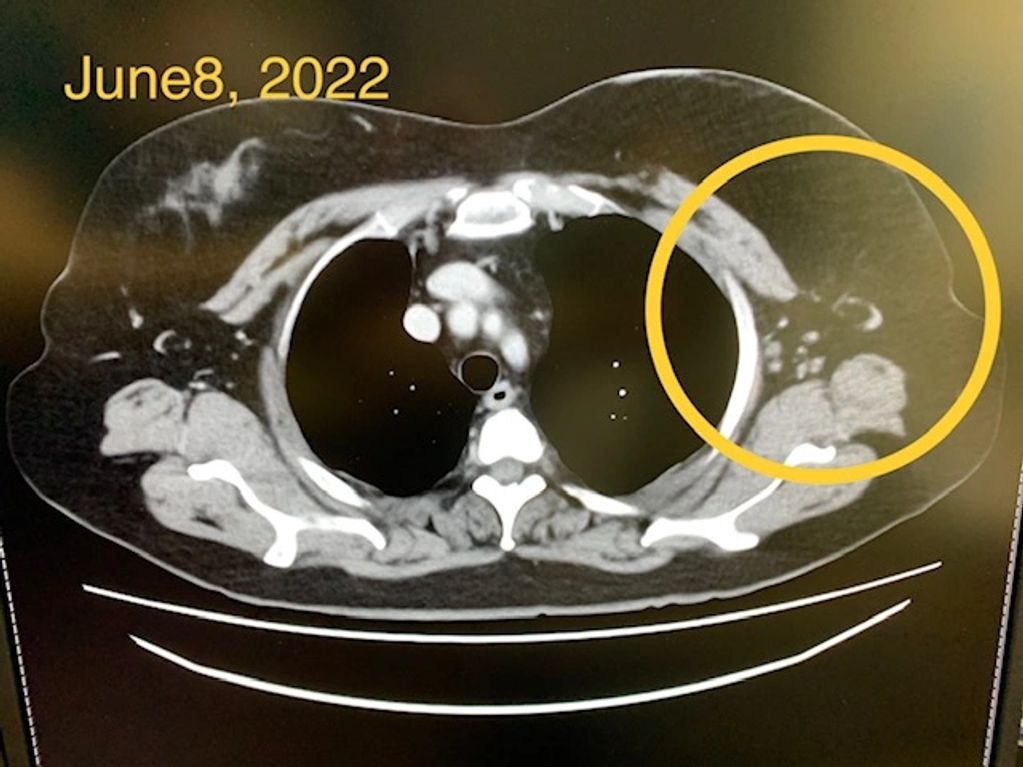

CT scan showing near complete resolution of breast tumors from treatment with a combination of methioninase and chemotherapy.